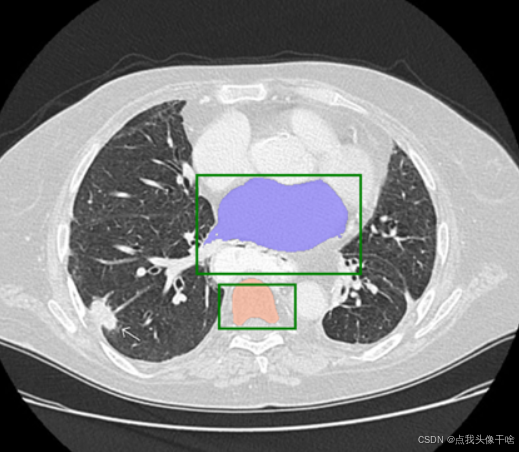

界面长这样:上面是几个按钮(上传图片、执行分割、清除点),中间是一块大画布。你上传一张图片,然后在想分割的地方点几下——左键点前景(绿色星星),右键点背景(蓝色星星)。点完了点“执行分割”,模型就开始工作,几秒钟后,分割结果就以红色半透明的形式叠加在原图上。

原版Swin-Unet只接受RGB三通道输入。我改成了四通道——前三通道是图片本身,第四通道是用户点提示。这样设计的好处是,模型可以在特征提取的早期就把提示信息和图像内容融合在一起,而不是等到后期才“想起来”还有提示这回事。

很多交互式分割方法只用正点(即用户想分割的区域),但我加了负点提示。别小看这个负点,在复杂场景下它能救命。比如你要分割一只趴在花丛里的猫,如果只点猫,模型可能把相似颜色的花也划进来;但如果再点几下花作为负点,模型就知道“哦,这种颜色虽然像猫,但不是猫”。